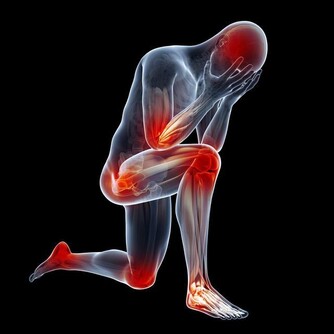

2、身體疲勞

經常感到全身疲憊,稍微做點事就會覺得累;每天即便睡眠充足,睡眠時間超過9個小時,但仍覺得困倦,精神不振,還容易分神。

4、癒合能力差

身體淤青後很難消下去;或者傷口相比其他人來說,癒合得很慢,很可能過了一段時間後還沒有完全癒合,而且還容易受到感染,出現紅腫、流膿的情況。